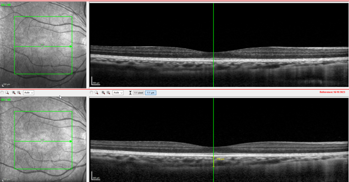

Figs 2 and 3. Patient one’s choroidal thickness pre-treatment (top) and at one-month follow-up

When he returned in February 2024 for his second follow-up, the axial length in both eyes had decreased significantly to R 26.00mm, L 26.05mm (Fig 1). There was also an increase in choroidal thickness from 276μm to 288μm (Figs 2 and 3). The patient has since continued on the combination therapy of ortho-k plus RLRL. He has been compliant with the three minutes, twice-a-day treatment, which is reported digitally to the clinic (Fig 4). OCT measurements did not show any loss of vision or damage to the retina.